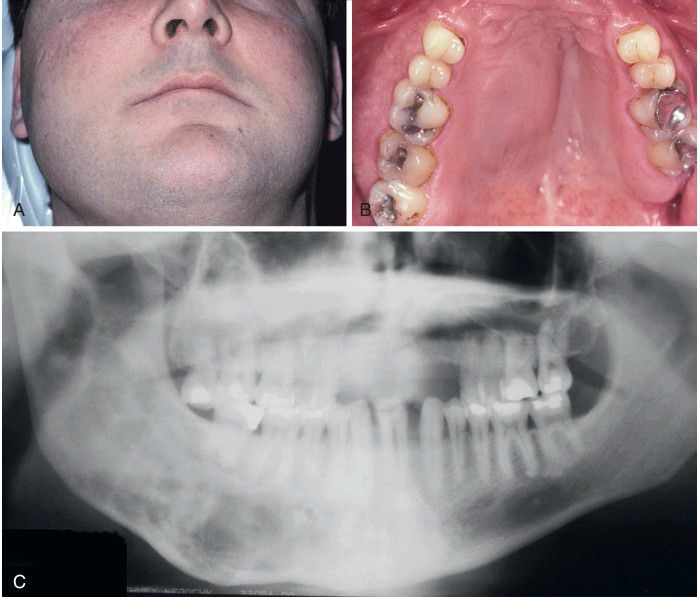

Polyostotic Fibrous Dysplasia

Jaffe-Lichtenstein syndrome. A, Young man exhibiting enlargement of the right maxilla and mandible. B, Intraoral photograph showing unilateral maxillary expansion. C, Panoramic radiograph showing ill-defined lesions of the right side of both jaws.